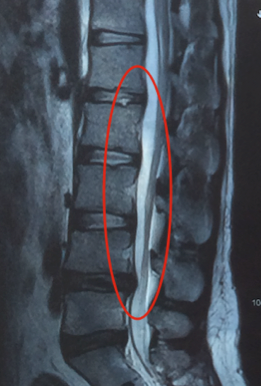

L’hèrnia del disc vertebral és la sortida del seu contingut, el nucli polpós, a través d’una fissura en l’embolcall fibrós del disc (Fig. 2).

Fig. 2